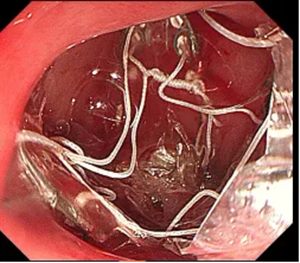

▲ 支架释放在肠道

这项创新的内镜下减重技术,通过在十二指肠及空肠上段置入一个特殊的、像袖套一样的支架,让食物物理性地“绕过”这段肠道,使其不再与肠液充分接触。这就像在肠道内搭建了一条“高架路”,让来自胃的食物快速通过,减少了与消化液的“交汇”。

其核心原理在于:通过减少这段关键肠道对脂肪和糖分的吸收,同时不影响蛋白质等必需营养的摄入,从源头上减少了热量的摄取。“患者不需要像以前那样忍受饥饿的痛苦,也不需要严格节食,依然能够达到理想的减重效果。”消化内镜中心郑权主任解释道。